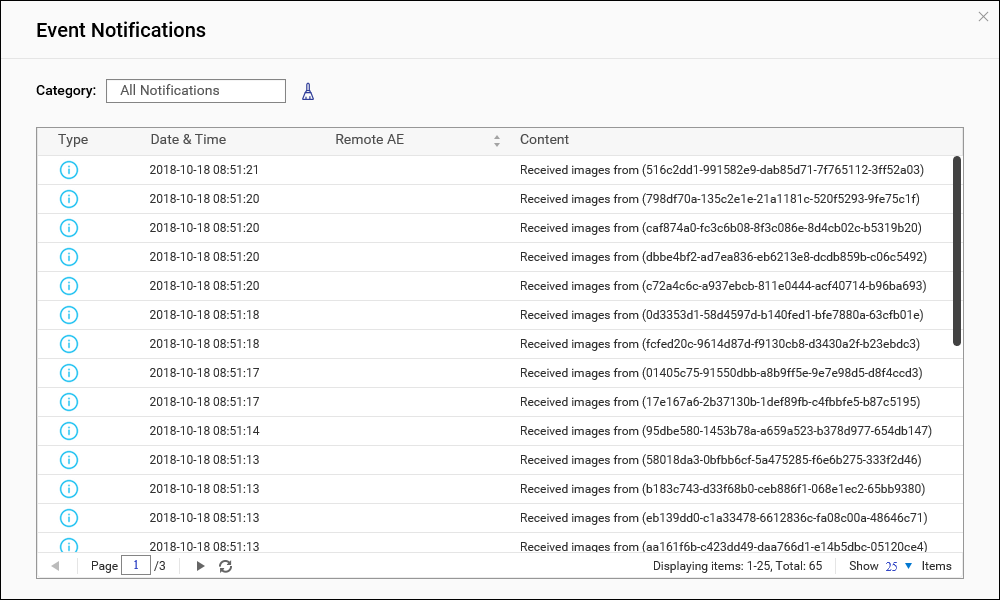

通知

用户可以在 MediQPACS 中管理通知。